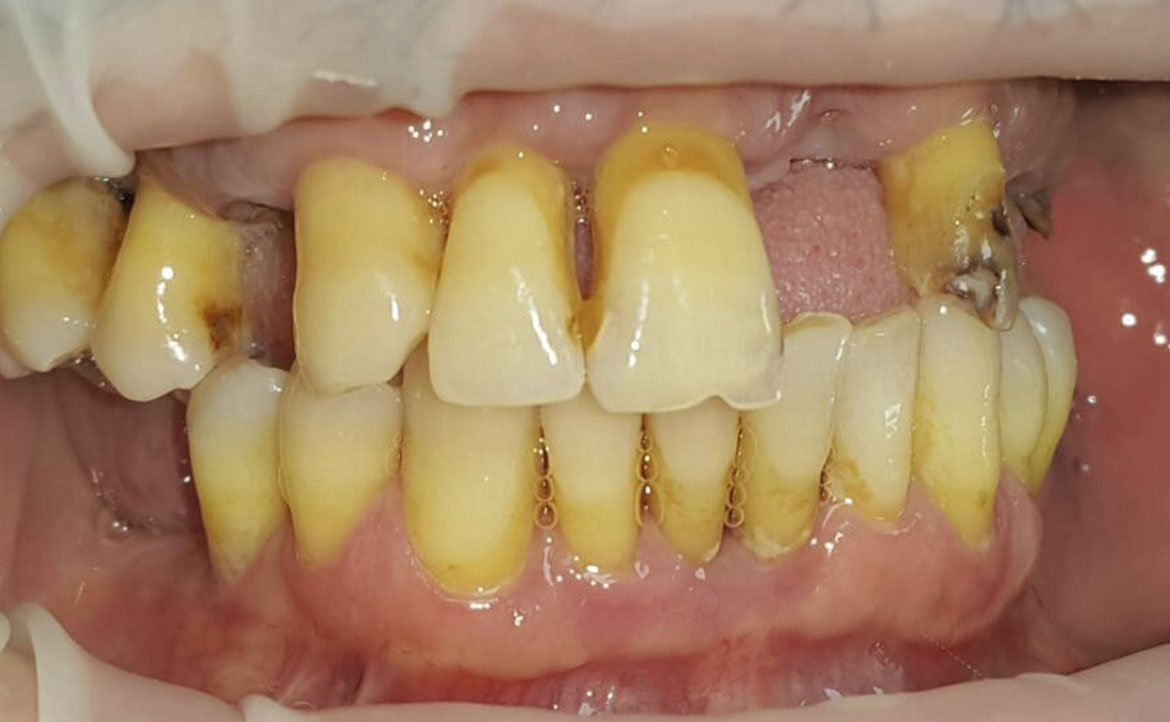

Oltre al ripristino estetico della dentatura, il ponte dentale previene le complicazioni che possono derivare dalla mancanza di un dente. Una volta applicato, completerà il normale processo di masticazione e migliorerà la funzione fonetica.